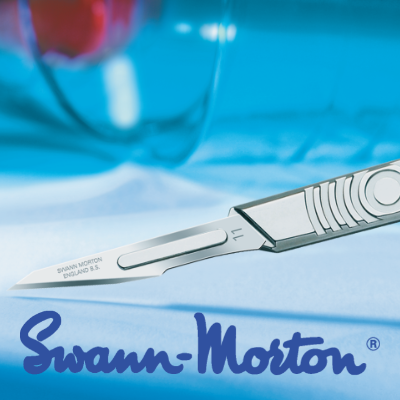

Swann Morton Standard Fitment Skin Graft Blades - Sterile

Skin graft blades for use with standard #3 fitment Swann Morton Handles.

Supplied as a box of 20 sterile, individually wrapped blades.

We are genuine UK Swann Morton Distributors

Precision, consistency and reliability have helped to establish Swann-Morton surgical blades and handles as the preferred brand of surgeons and health care professionals in all corners of the World.